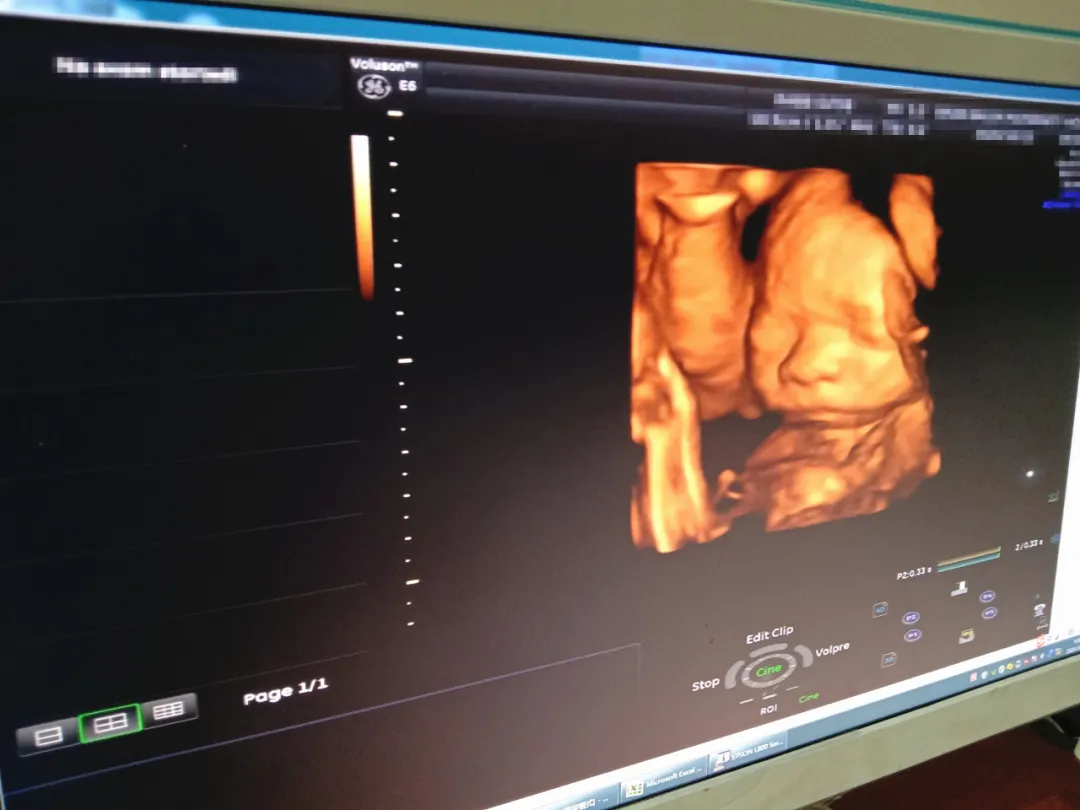

相信不少孕妈们在做超声影像(四维彩超)时都遇到过这些情况。这时,孕妈们只能出去溜达溜达再回到超声诊室碰碰运气,如果宝宝位置还是不好,有时得在医院待一天,甚至改天再来。

超声影像(四维彩超)的立体成像效果及清晰度,受孕妈胎位情况及宝宝的配合程度而定。